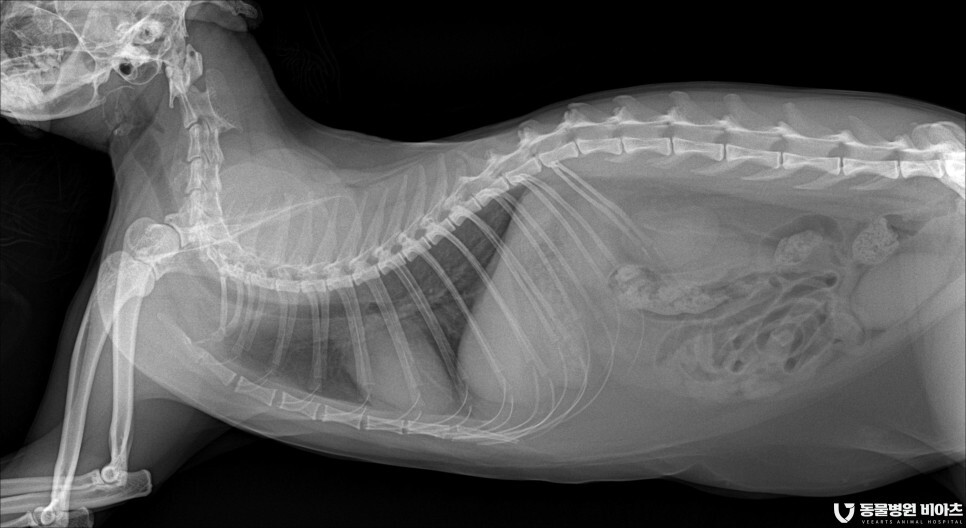

엑스레이 촬영

흉부 엑스레이와 발톱 부위의 엑스레이 촬영을 합니다.

마취 전 검사와 병변 부위의 검사입니다.

병변 부위를 제외하고는 특이 소견이 없었습니다.